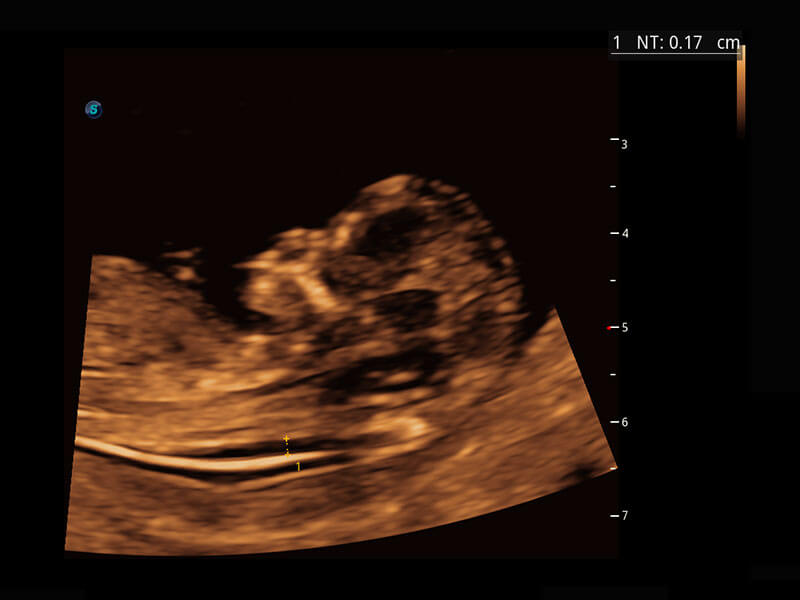

P60在胎兒早孕期超聲篩查中為您帶來(lái)優(yōu)異的圖像質(zhì)量。

早孕-胎心

高分辨率容積成像-早孕胎兒